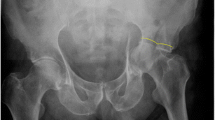

The baseline stiffness values for the synthetic tissue surrogates (n = 2) and cadaveric specimens (n = 2) were 927 and 894 N/mm and 541 and 535 N/mm, respectively. Both cadaver specimens failed during cyclic testing at 1.5 × BW (1050 N). Failure of the specimens was manifested as progressive medial subluxation of the femoral head associated with displacement of the distal fracture fragment medially and rotation of the distal fracture fragment posteriorly about the osteotomy line. Failure occurred progressively as the head of the posterior column lag screw plowed through the osteoporotic trabecular bone and cortex beneath the quadrilateral surface (Fig. 3A–B). The failure mechanisms were identical for the two cadaveric specimens. The synthetic specimens both survived the incrementally increasing load protocol. When loaded to failure, these specimens failed in a manner identical to that of the cadaveric specimens. Fracture was evident on the quadrilateral surface for both specimens and initiated on the ilium side of the osteotomy at the posterior column lag screw/cortical bone interface (Fig. 3B–C).